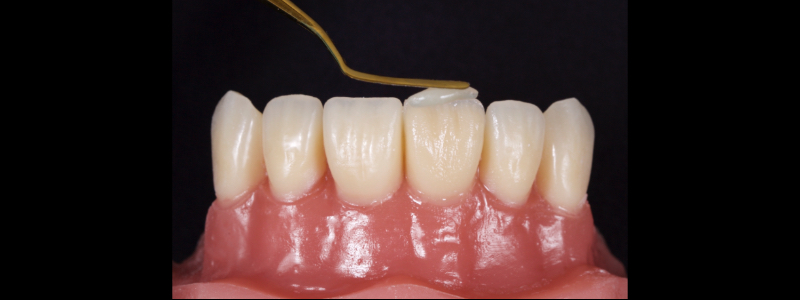

To achieve this, the achromatic enamel mass is first placed on a PVS Putty stent made from a diagnostic wax-up with a flat plastic (see the first article in this series for more detail). The enamel mass is thinned with a flat plastic in combination with a multipurpose condenser, a #3 brush (i.e., GC, Cosmedent, Tokuyama), and some modeling resin (Fig. 7).

A modeling resin is a liquid resin that does not contain HEMA — examples include modeling resin (Bisco), Brush and Sculpt (Cosmedent), and Signum (Kulzer). The unpolymerized resin is then carried in the stent to the tooth and adapted to the palatal margin with a #3 brush (Fig. 8).